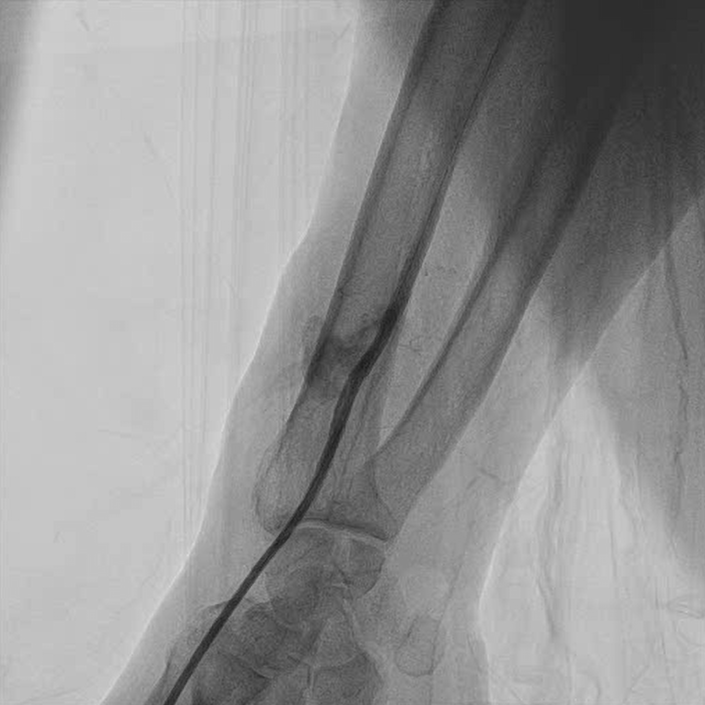

Because of the absence of injectable thrombin solution and the frail condition of the patient, it was decided to proceed with an endovascular approach. A 6F sheath was introduced in the distal radial artery (Figures 1 and 2, Video 1). Using a 6F Judkins catheter, a 0.014-inch guidewire was introduced inside the radial artery through the base of the RPA and distal to the brachial artery. A 3 x 24-mm polytetrafluoroethylene-covered stent was deployed initially, but with residual leak (Figure 3, Video 2). A second 3 x 18-mm covered stent was deployed, with minimal contrast flow inside the RPA. Final post-dilatation was performed with a 3.5 x 15-mm noncompliant balloon, with no residual flow inside the pseudoaneurysm. (Figure 4, Videos 3 and 4).